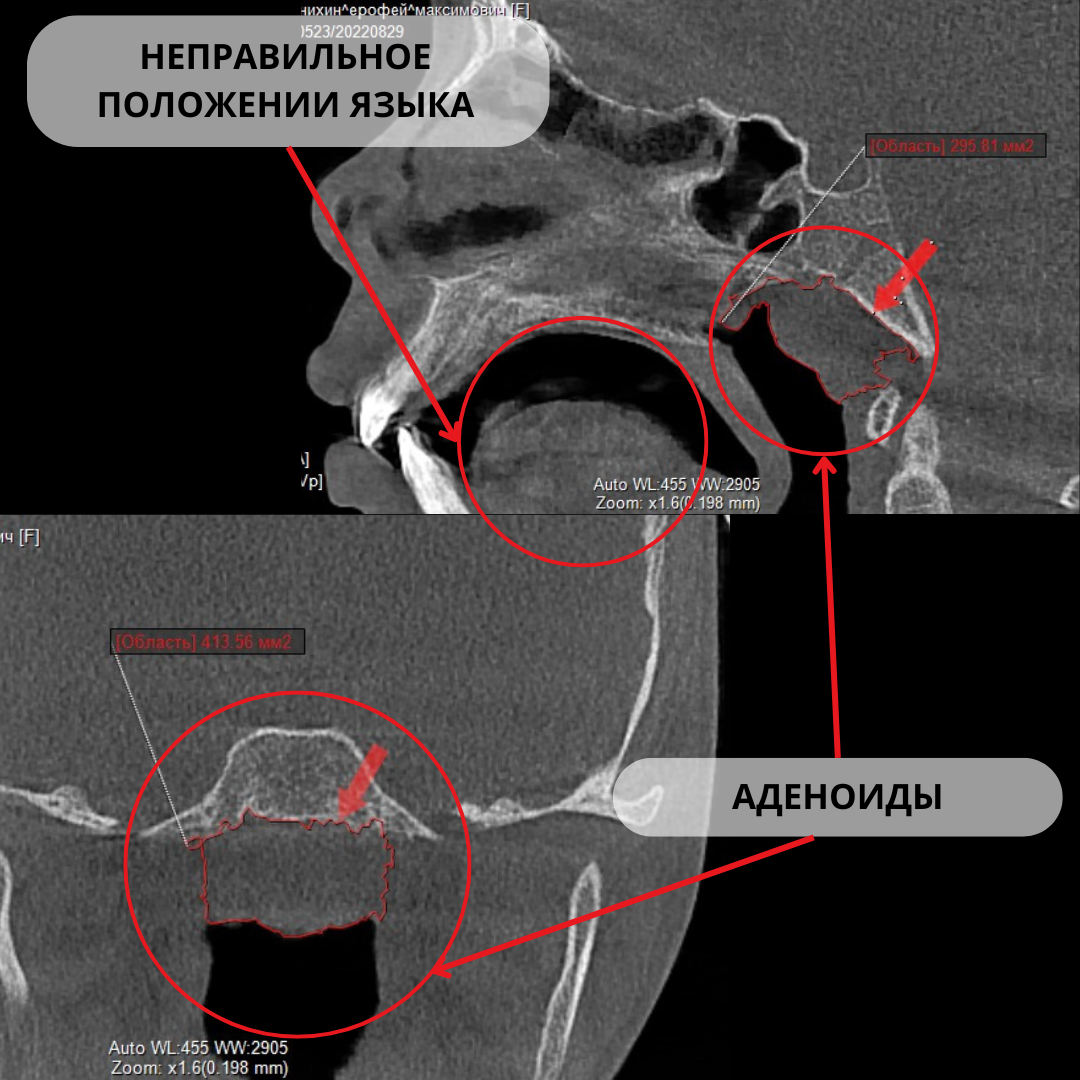

После комплексного обследования, включающего КТ, фотопротокол и слепки, мы обнаружили:

• Узкие верхняя и нижняя челюсти.

• Неправильный прикус.

• Смешанный тип дыхания с преобладанием ротового дыхания.

• Нижнее положение языка, открытый рот и ослабленный тонус губ.

• Наличие аденоидов.

Эти факторы оказали негативное влияние на развитие челюстей и формирование правильного прикуса.

Лечение не затронуло первопричины:

• Аденоиды продолжали блокировать носовое дыхание.

• Ротовое дыхание сохранялось, язык оставался в нижнем положении, не поддерживая верхнюю челюсть.